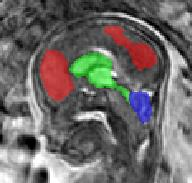

Limiting failures of machine learning systems is of paramount importance for safety-critical applications. In order to improve the robustness of machine learning systems, Distributionally Robust Optimization (DRO) has been proposed as a generalization of Empirical Risk Minimization (ERM). However, its use in deep learning has been severely restricted due to the relative inefficiency of the optimizers available for DRO in comparison to the wide-spread variants of Stochastic Gradient Descent (SGD) optimizers for ERM. We propose SGD with hardness weighted sampling, a principled and efficient optimization method for DRO in machine learning that is particularly suited in the context of deep learning. Similar to a hard example mining strategy in practice, the proposed algorithm is straightforward to implement and computationally as efficient as SGD-based optimizers used for deep learning, requiring minimal overhead computation. In contrast to typical ad hoc hard mining approaches, we prove the convergence of our DRO algorithm for over-parameterized deep learning networks with ReLU activation and a finite number of layers and parameters. Our experiments on fetal brain 3D MRI segmentation and brain tumor segmentation in MRI demonstrate the feasibility and the usefulness of our approach. Using our hardness weighted sampling for training a state-of-the-art deep learning pipeline leads to improved robustness to anatomical variabilities in automatic fetal brain 3D MRI segmentation using deep learning and to improved robustness to the image protocol variations in brain tumor segmentation. Our code is available at https://github.com/LucasFidon/HardnessWeightedSampler.